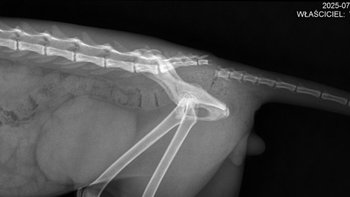

Kochani! Przedstawiam Wam siwiutką Asti - nową podopieczną na pokładzie - Asti w sobotę bardzo źle się czuła - po…